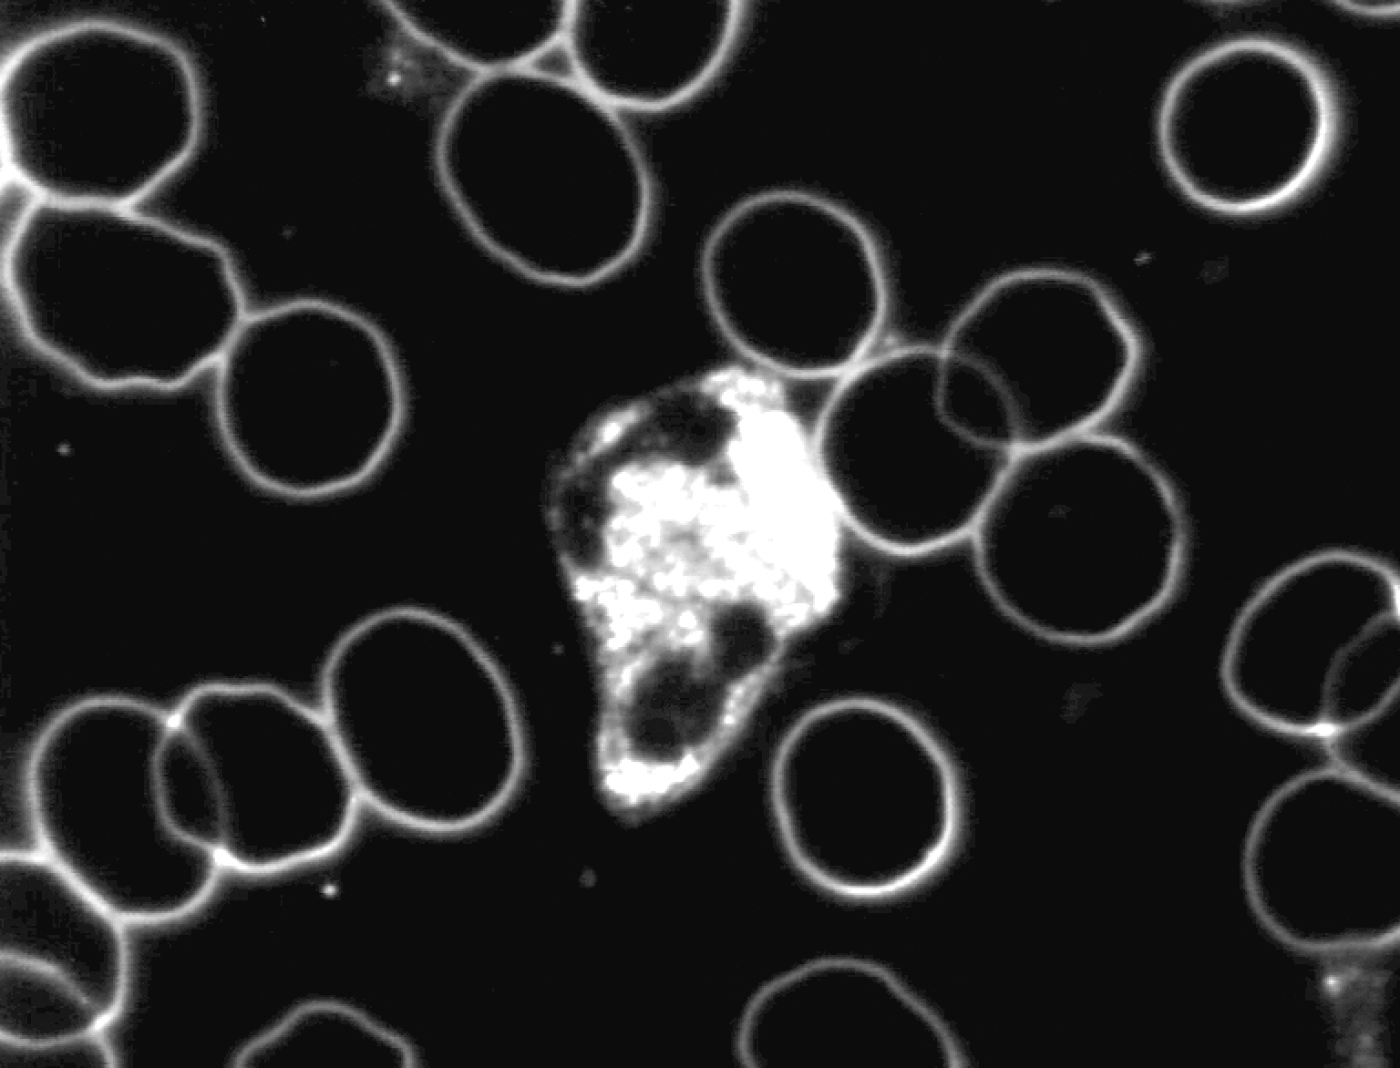

Zie ook onderstaande foto’s met een karakteristiek beeld van vóór en na de neutralisatie met Benzoliet.

Levend bloedbeeld

vóór neutralisatie met Benzoliet

De veranderingen die we hebben geconstateerd in met name de witte cellen na blootstelling aan technische en geopathische verstorende subtiele energieën, waren:

- afname van beweeglijkheid van de cel

- het aannemen van de bolvorm

- afgenomen en op een plek geconcentreerde cytoplasmatische activiteit

Onze conclusie is dat de effectiviteit van het immuunsysteem onder invloed van de subtiele verstorende energieën vermindert.